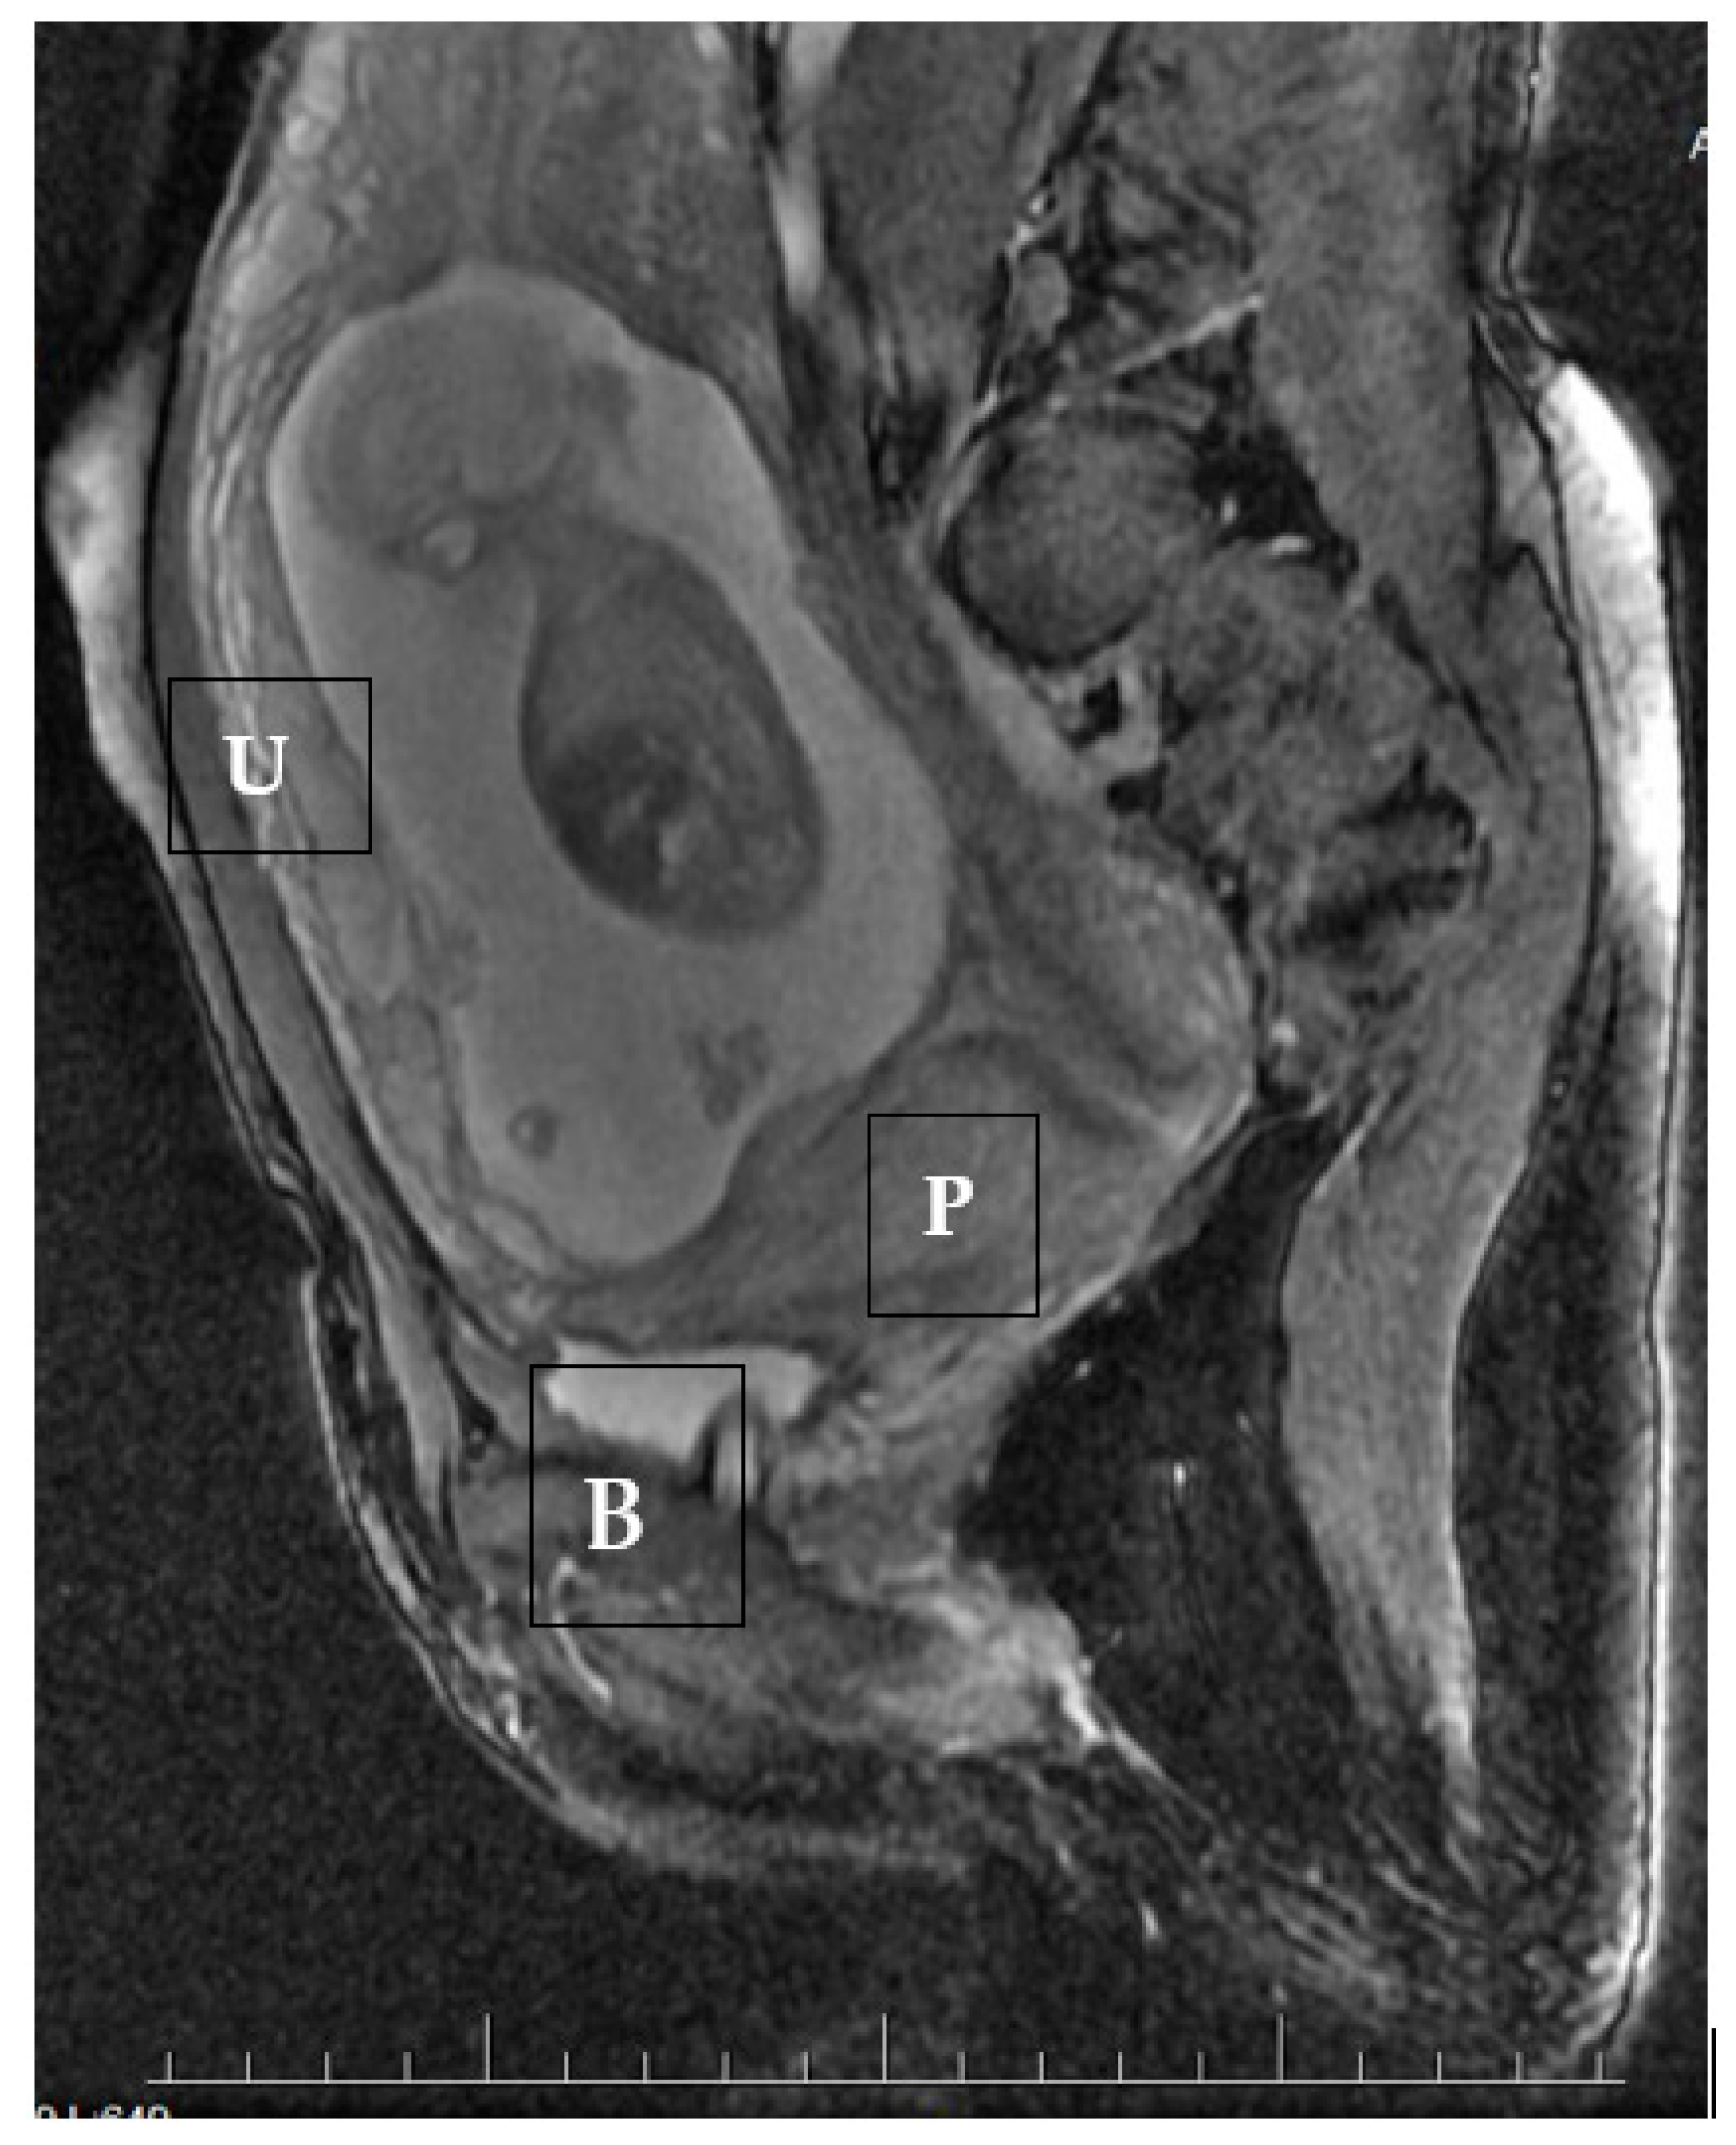

1.2. Case 2